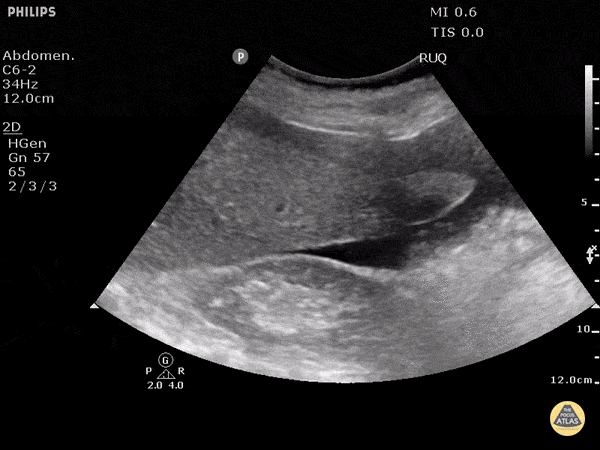

A 20- something year old male is dropped off at a community ED after a gunshot wound to the lower back. He will quickly be placed in a resuscitation bed and placed on monitors. His initial vitals will include tachycardia but no hypotension. The team will proceed through their primary survey and identify only one gunshot wound. If they do not recognize possible free fluid and the need for blood, the patient will become increasingly hypotensive. They will be required to intubate the patient while waiting for the staff surgeon to arrive in order for the patient to go to the OR.